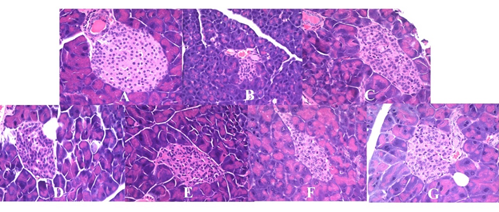

图2 不同剂量GABA酸奶对胰腺形态的影响

本研究将发酵好的酸奶按照不同剂量对2型糖尿病小鼠进行饮食干预,研究发现不同剂量的GABA酸奶在不同程度改善糖尿病相关指标,如增加血清胰岛素和脂肪指数、降低血液中尿素氮水平、减少葡萄糖曲线下面积和胰岛素敏感性指数等;其中,高剂量的GABA酸奶在改善胰岛素敏感性方面优于低剂量组,主要体现在HOMA-β、总胆固醇、高密度脂蛋白、脂肪指数和胰岛细胞形态等方面。这一工作为揭示富含GABA发酵食品的营养价值和新型功能性食品的开发利用提供了理论借鉴